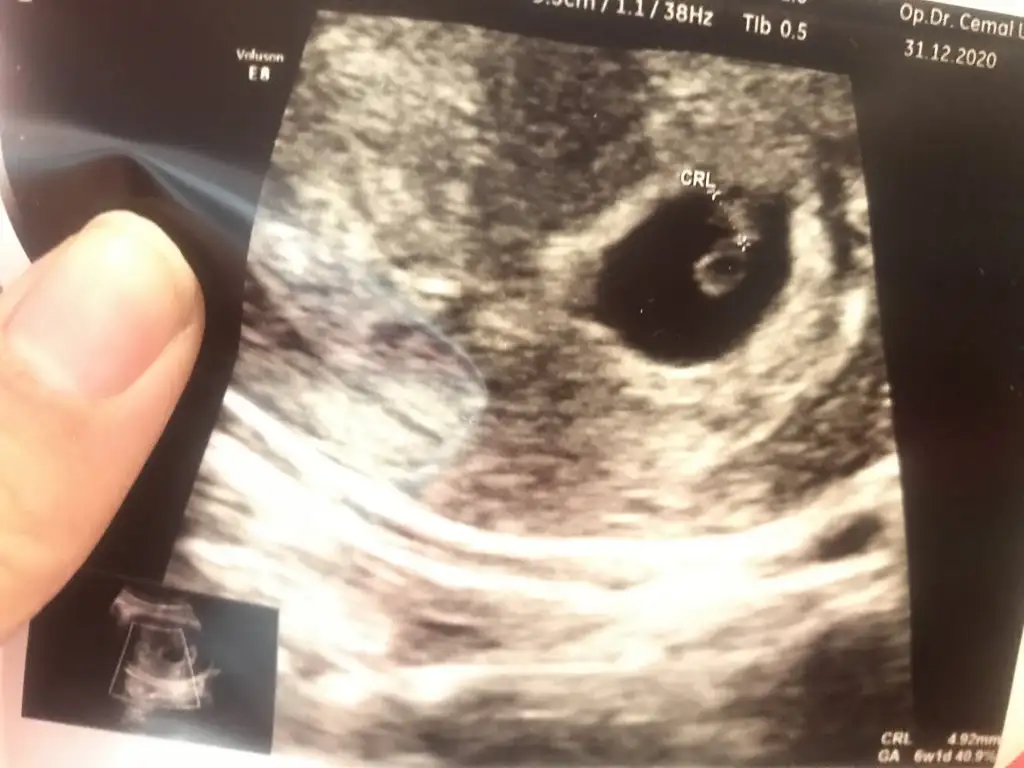

İlk ultrason resimlerinizi paylaşın ramzi teorisine göre cinsiyeti tahmin edeyim bakalım tutacak mı?

6 haftalık. Sizce nedir?